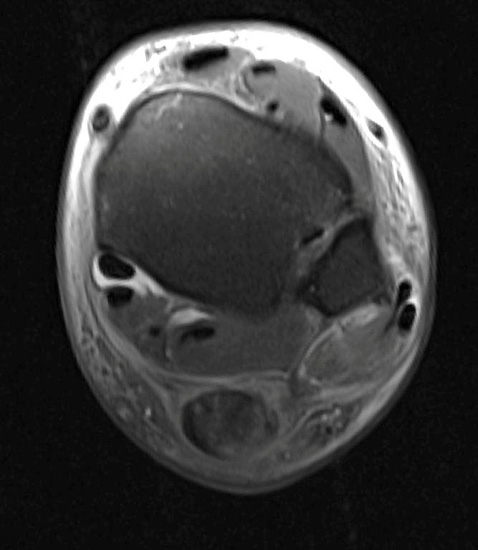

• Ggf. Magnetresonanztomographie des Rückfußes mit Kontrastmittel in Bauchlage und Plantarflexion des Fußes zur Beurteilung der Sehnen und des Bandapparates 20. Die Aussagekraft der MRT ist bezüglich gleichzeitiger Schäden der Sehnen gut. Die Instabilität selbst kann durch eine MRT Untersuchung nicht abschließend ausgeschlossen werden, da Untersuchung oft nicht im Stadium der akuten Luxation durchgeführt wird (Abbildung 3). Dagegen erlaubt die dynamische Untersuchung mit Ultraschall eine präzise Beurteilung der Sehnenstabilität 21.